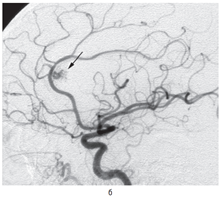

Геморрагический инсульт следует дифференцировать прежде всего от ишемического, составляющего до 80–85% всех инсультов. Поставить точный диагноз необходимо, чтобы как можно раньше начать соответствующую терапию. Дифференциальная диагностика по клиническим данным не всегда возможна, поэтому необходимо госпитализировать больных с диагнозом «инсульт» в стационары, оснащенные КТ- или МРТ-оборудованием. Для ишемического инсульта характерны более медленное нарастание общемозговых симптомов, отсутствие в большинстве случаев менингеальных симптомов, в ряде случаев — наличие предвестников в виде ПНМК, нарушения сердечного ритма в анамнезе. Ликвор при ишемическом инсульте обычно имеет нормальный состав, в то время как при геморрагическом — в большинстве случаев содержит примесь крови. Исключение составляют малые, не сообщающиеся с ликворными путями гематомы, при которых макроскопически ЦСЖ не изменена. Необходимо подчеркнуть, что при общем тяжелом состоянии больного, особенно при наличии стволового синдрома, люмбальную пункцию лучше не делать или выполнять с большой осторожностью, поскольку выведение ликвора может вызвать дислокацию головного мозга. Внутримозговые гематомы гипертонического генеза необходимо также дифференцировать от гематом другой этиологии, а также от кровоизлияний в очаг ишемии или опухоль. Большое значение при этом имеют анамнез заболевания, возраст больного, локализация гематомы в веществе мозга. При кровоизлиянии из аневризмы гематомы имеют типичную локализацию — медиобазальные отделы лобной доли при аневризмах передней мозговой/передней соединительной артерии (рис. 12.4) и базальные отделы лобной и височной долей, прилежащие к сильвиевой щели, при аневризмах внутренней сонной или средней мозговой артерии. При МРТ можно также видеть аневризму или патологические сосуды артериовенозной мальформации (рис. 12.5). При подозрении на разрыв аневризмы или артериовенозной мальформации, на что в первую очередь может указывать молодой возраст больного, необходимо проведение ангиографического обследования.

img93

Рис. 12.4. Типичная локализация внутримозговой гематомы при разрыве аневризмы передней мозговой/передней соединительной артерии (компьютерная томограмма). Видна гематома медиобазальных отделов левой лобной доли (а) с прорывом в желудочковую систему (б)